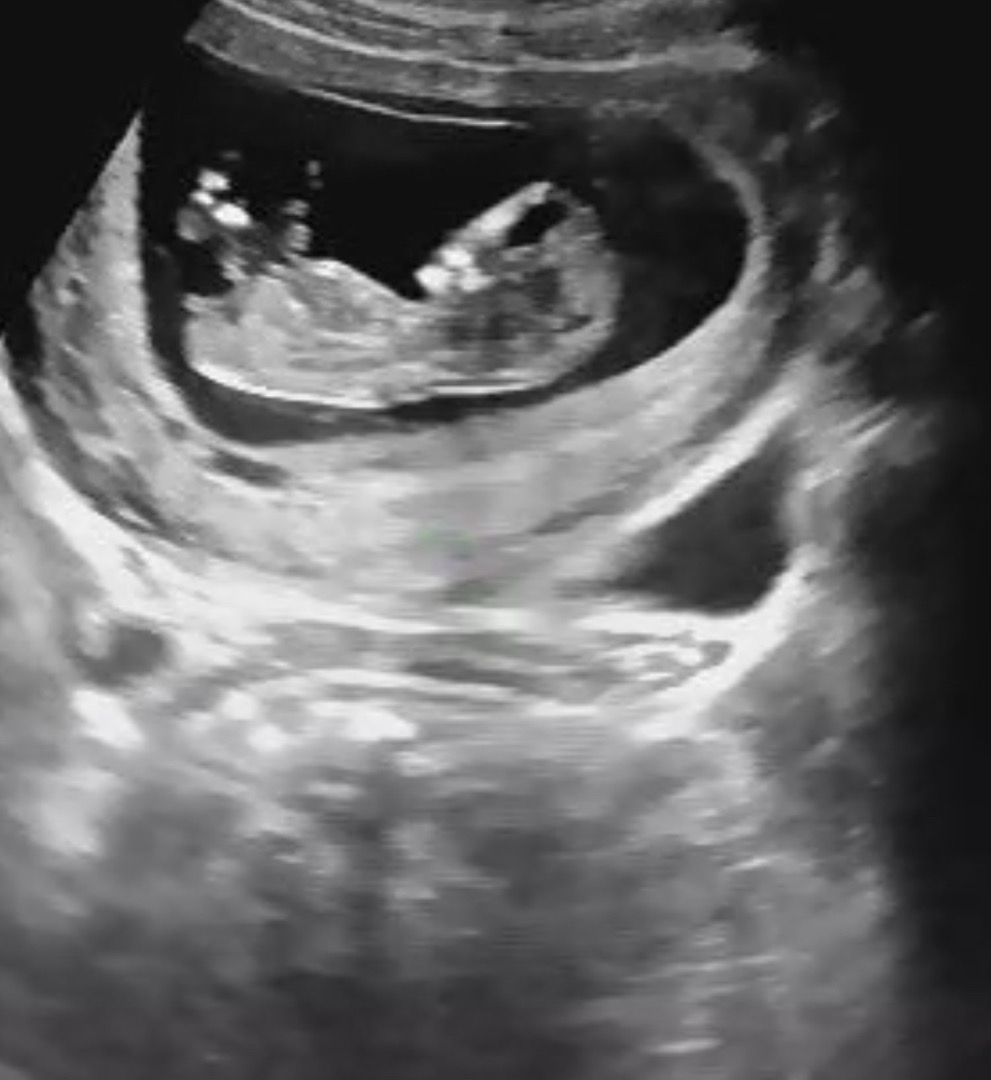

다리사이에 아무것도 없어서 딸 확률 높대요>_< 각도법 어떤가요!!